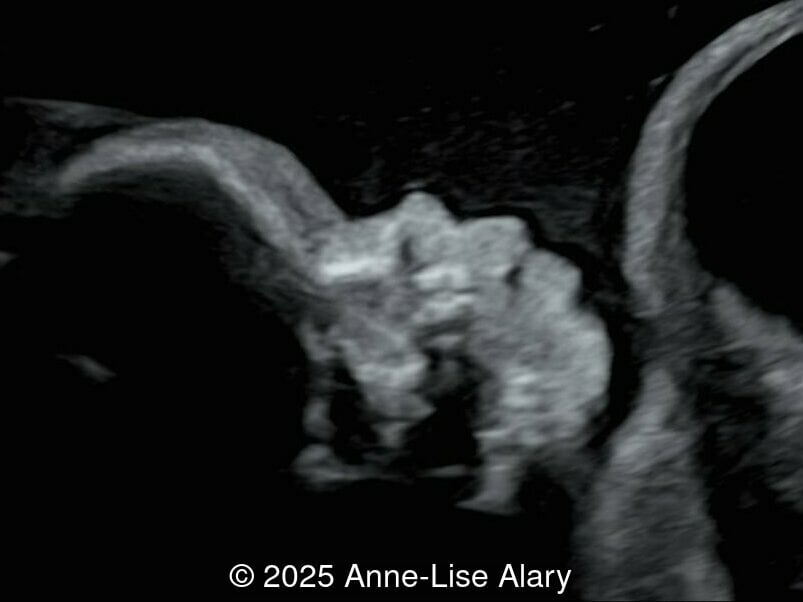

20-year-old primigravid woman, presented late for prenatal care at 29 weeks gestation. There was no consanguinity, and no pertinent past medical or familial history. We found the following anomalies:

We present a case of Prune Belly Syndrome

Our prenatal ultrasound revealed a male fetus with megabladder, dilation of both ureter and kidneys, and thinned kidney parenchyma consistent with Lower Urinary Tract Obstruction (LUTO).  Additional findings suspected on ultrasound and confirmed on computed tomography included:

• Short long bones (<1st percentile), normal mineralization, and no sign of lethal chondrodysplasia

• Evidence of Potter's sequence due to the lower urinary tract obstruction with small thorax compared to the abdomen, hyperextended neck, and pes varus.

• Dysostosis: Hemivertebrae L3, fused L4-L5, abnormal left foot with short metatarsals and missing phalanges

• Suspicion of dilated bowel in the left flank, in addition to dilated urinary tract

The diagnosis of PBS is often made in the second trimester of pregnancy, although it has been described as early as 11 weeks of gestation [20]. The most frequent ultrasound findings are a large, thin-walled bladder accompanied by bilateral hydroureter/hydronephrosis, dysplastic kidneys with echogenic renal parenchyma and renal cortical cysts, and abdominal wall laxity which is better viewed after bladder decompression [21]. Cryptorchidism can be detected prenatally by 28 to 30 weeks gestation when the testes descend into scrotum. There may be a patent urachus, visible as a cystic connection between bladder and umbilicus. Oligohydramnios is a frequent finding, which makes it difficult to visualize the associated anomalies.